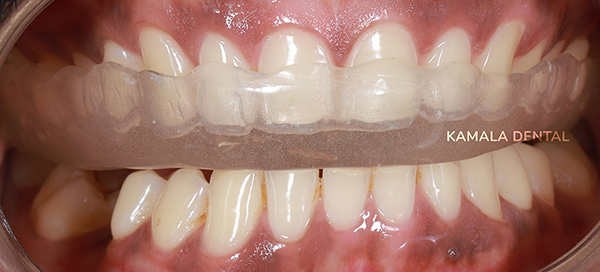

- Occlusal Splints & Night Guards: Custom-made removable appliances designed to reduce stress on the TMJ, correct bite interferences, and protect teeth from grinding-related damage.

- Therapeutic Treatment: Could include splints, injections, exercises, or minor dental corrections.